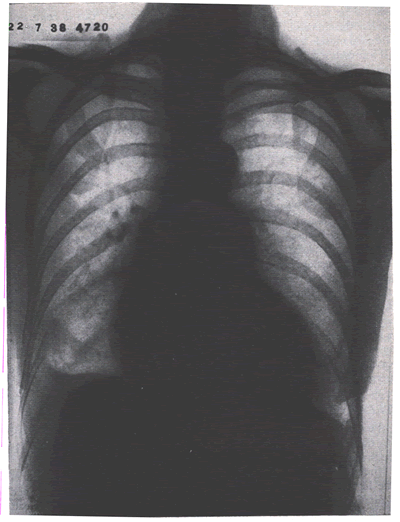

In addition, the patient should undergo chest radiography(DIAGPEXray-fig.8')

and electrocardiography. Although the latter tests are often

not helpful, they can be useful in ruling out other disorders

that simulate PE. In addition, a chest radiograph is required

for proper interpretation of the perfusion lung scan.

DIAGPEXray-fig.8': Patient with massive pulmonary embolism

obstructing the left main pulmonary artery.Note the uneven distribution

of pulmonary blood flow between the two lungs in favor of the

right.

The chest radiograph is rarely, if ever, diagnostic(DIAGPEXray-fig.8').

It may show a pneumothorax, pulmonary edema, or findings suggestive

of primary or secondary malignancy. The finding of a Hampton

hump (a semicircular opacity with the base abutting the pleural

surface) is strongly suggestive of pulmonary infarction(DiagPEXray-fig.8''),

but in the vast majority of patients chest radiography findings

are nonspecific or normal. Other radiographic features compatible

with PE include pleural effusion, subsegmental atelectasis,

pulmonary infiltrate, raised hemidiaphragm, regions of apparent

oligemia(DIAGPEXray-fig8 ,see above), or a prominent pulmonary

vascular shadow at the hilum. However, none of these features

are diagnostic of PE because they can be produced by other conditions,

including obstructive lung disease, pulmonary infection, or

atelectasis.

DiagPEXray-fig.8'': -Skiagram showing a small pulmonary infarct

at the right base with a little hemmorrhagic effusion.